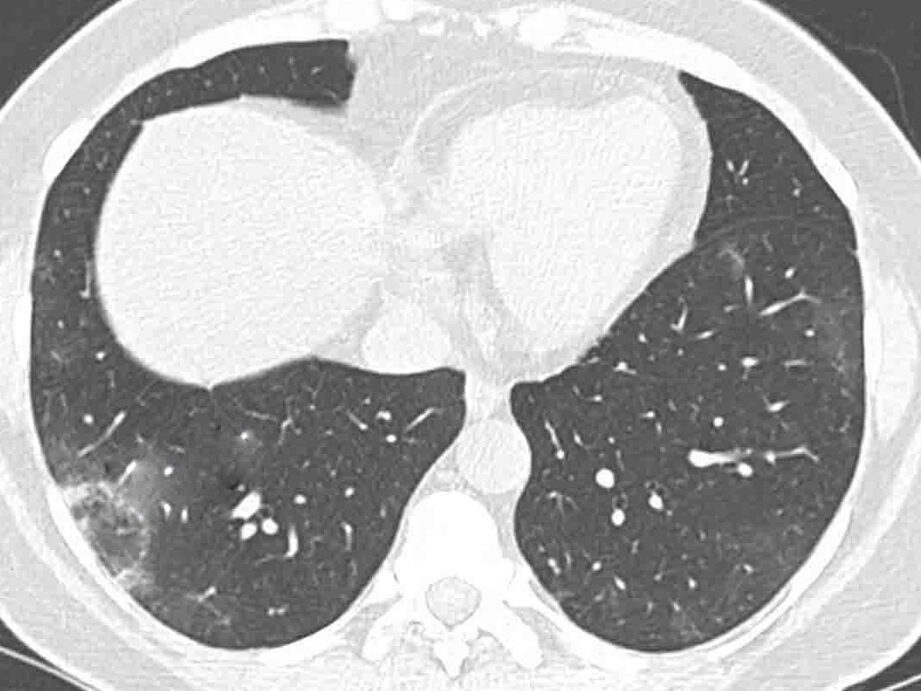

La tomografía de tórax es un examen de imagen muy utilizado para diagnosticar enfermedades pulmonares y evaluar el estado de los pulmones, los vasos sanguíneos y los huesos del tórax. Este procedimiento es de gran utilidad en el diagnóstico y seguimiento de enfermedades como COVID-19, neumonía, fracturas, nódulos y tumores. Además, la tomografía de tórax también puede utilizarse para identificar hematomas en el tórax y evaluar el estado del tórax antes y después de cirugías.

La tomografía de tórax es una herramienta vital en el diagnóstico de enfermedades pulmonares, permitiéndonos obtener imágenes detalladas y claras de los pulmones, los vasos sanguíneos y los huesos del tórax.